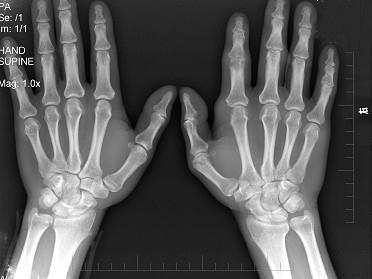

问题 男,19岁,双手肿痛2年,早晨起床前活动受限,请结合所提供图像,选择最佳选项 ( )

选项 A、退行性关节炎 B、未见异常 C、强直性脊柱炎 D、类风湿关节炎 E、痛风

答案 D